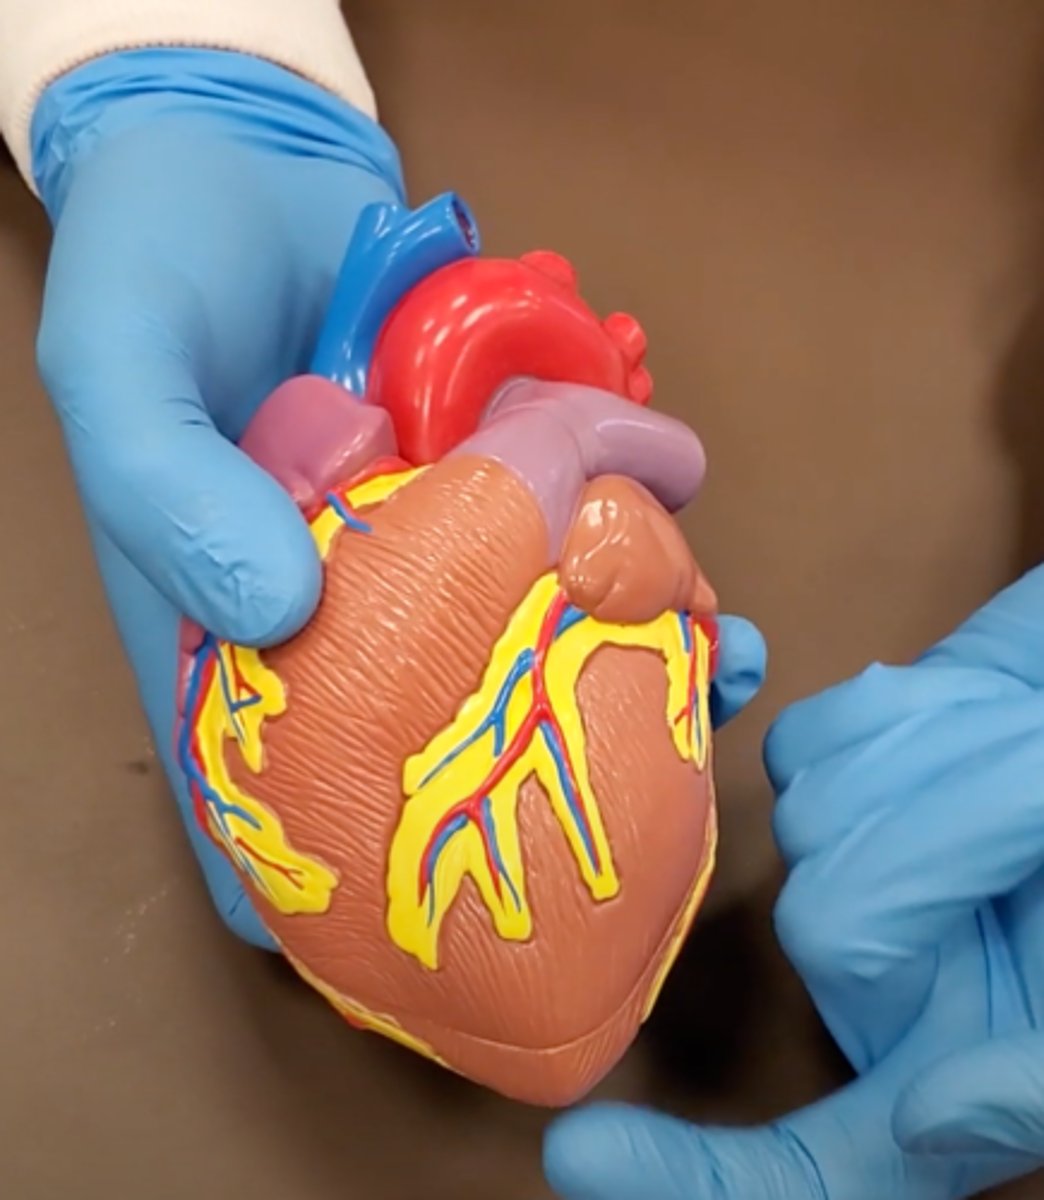

pulmonary trunk (model)

yellow sash of fat that tells you this if the front side of the heart (model)

t-shaped ribbon of fat on back side of heart (model)

Left ventricle (model)

has the most muscle mass because it has to pump blood to the whole body

apex (model)

base (model)

where everything connects